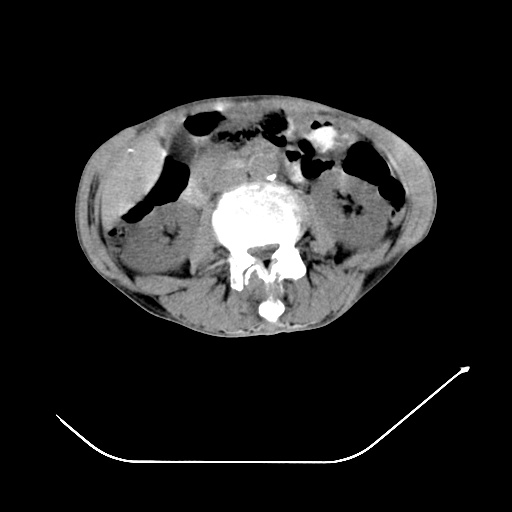

以下是引用zsl6918在2008-8-25 21:55:00的发言:[br]符合右肺周围性肺癌并肺内转移,左肺结核球。双肺肺气肿。腰椎附件转移。

以下是引用随光逐影在2008-8-25 22:03:00的发言:[br]1)考虑右肺下叶周围性肺癌并肺内转移,腰椎附件转移。2)左上肺结核(结核球形成)。3)双肺肺气肿(多发肺大泡形成)。4)双肺门区及纵隔内多发淋巴结钙化。